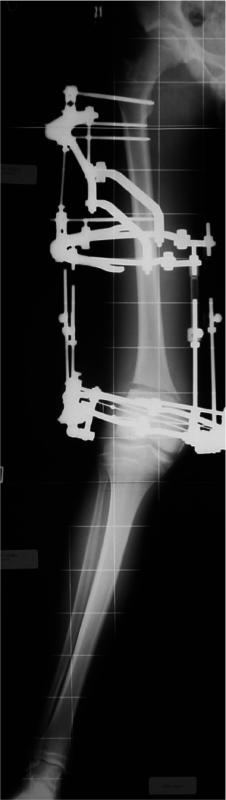

1 mese

3 mesi